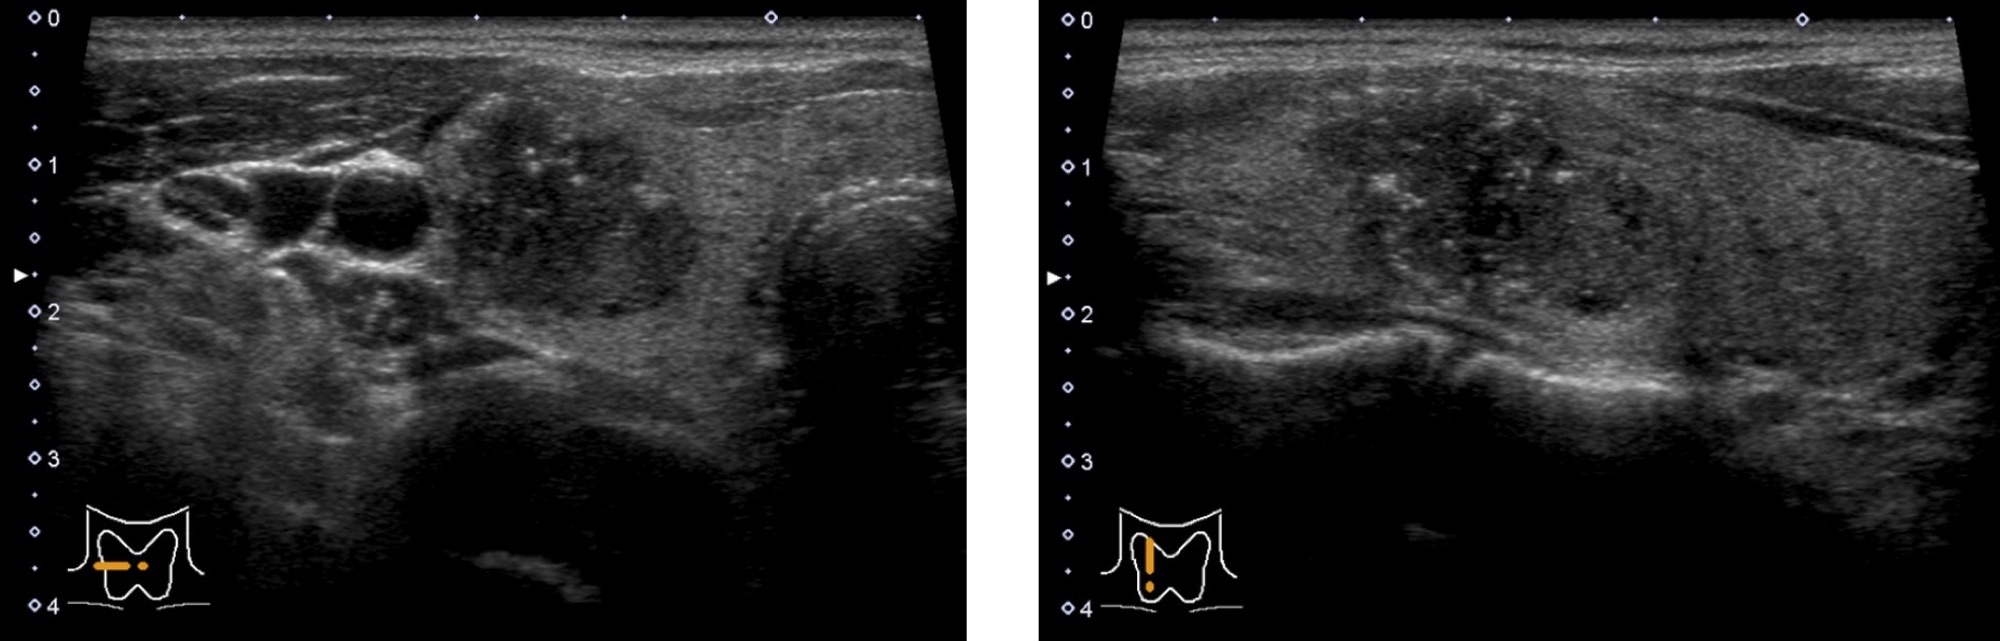

正常甲状腺 の超音波画像

正常な甲状腺は、周りの筋肉よりも白く (エコーレベルが高く) 見えます。

バセドウ病

甲状腺全体が腫れて大きくなり、血流が多くなります。

※軽症の場合は正常な甲状腺とほとんど変わらない場合もあります。

無痛性甲状腺炎

血液検査ではバセドウ病と同様に甲状腺ホルモンの値が高くなりますが、超音波画像ではバセドウ病と比べて血流が少ないのが特徴です。